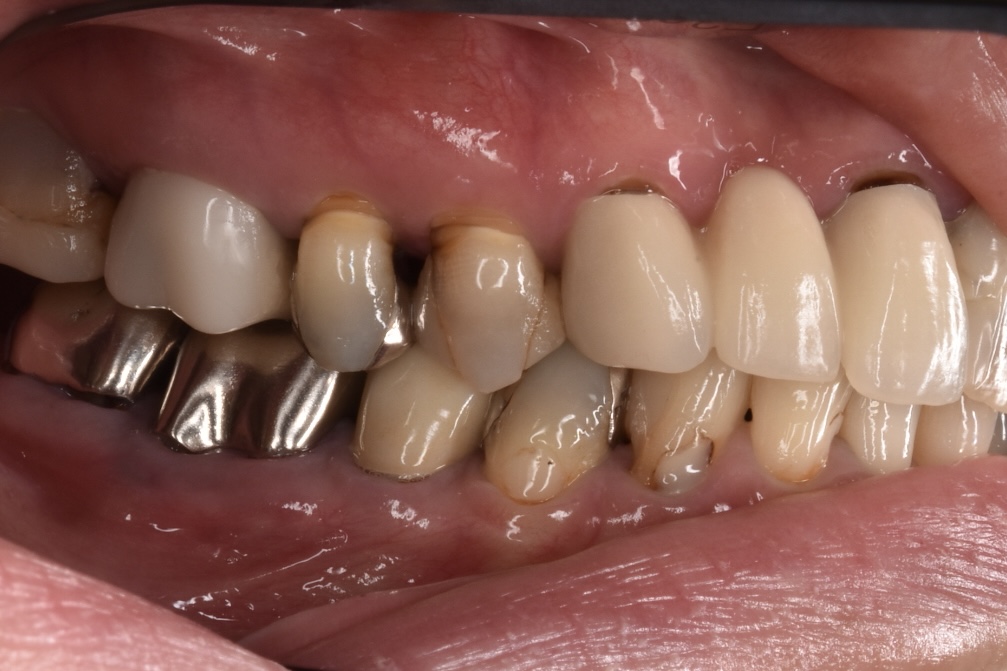

初診時の状態

各歯が自費の被せ物や保険の治療痕など歯ごとにバラバラな状態で、どれも状態が良いとは言えないものばかりでした。見た目の回復も必要ですがそれ以前に再神経処置・虫歯再治療・抜歯、噛み合わせの回復など多岐にわたる治療が必要な状態でした。